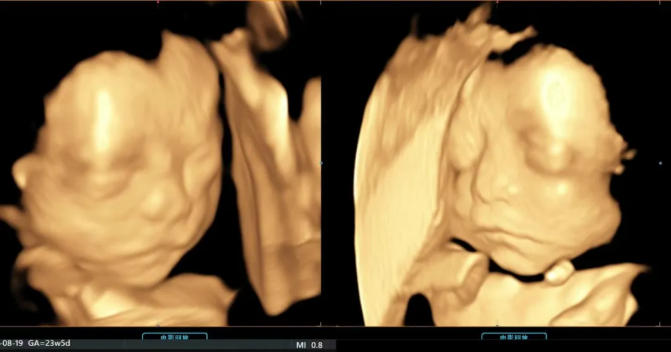

而四维彩超,就是孕期里最浪漫的“约会”

跨越肚皮的阻隔,清晰看见宝宝的模样

定格生命最初的美好,也为宝宝的健康保驾护航

艾玛妇产拥有超声影像进口GE设备,作为前沿器械,可以堪称为妇产领域超声的“战斗机”,其带来的强劲处理能力,成就了全新的渲染重建技术,全面颠覆传统视觉理念,带来前所未有的影像质量。同时能够提供更多的图像数据,实现在扫描同时即刻呈现胎儿标准生长曲线和相应测量数据,实时的结构信息及功能成像为临床精确诊断和评估提供坚实可靠的图像支持。

六 四维影像留念

医生在做筛查时会抓取部分照片和视频片段赠送给宝爸宝妈以作留念。